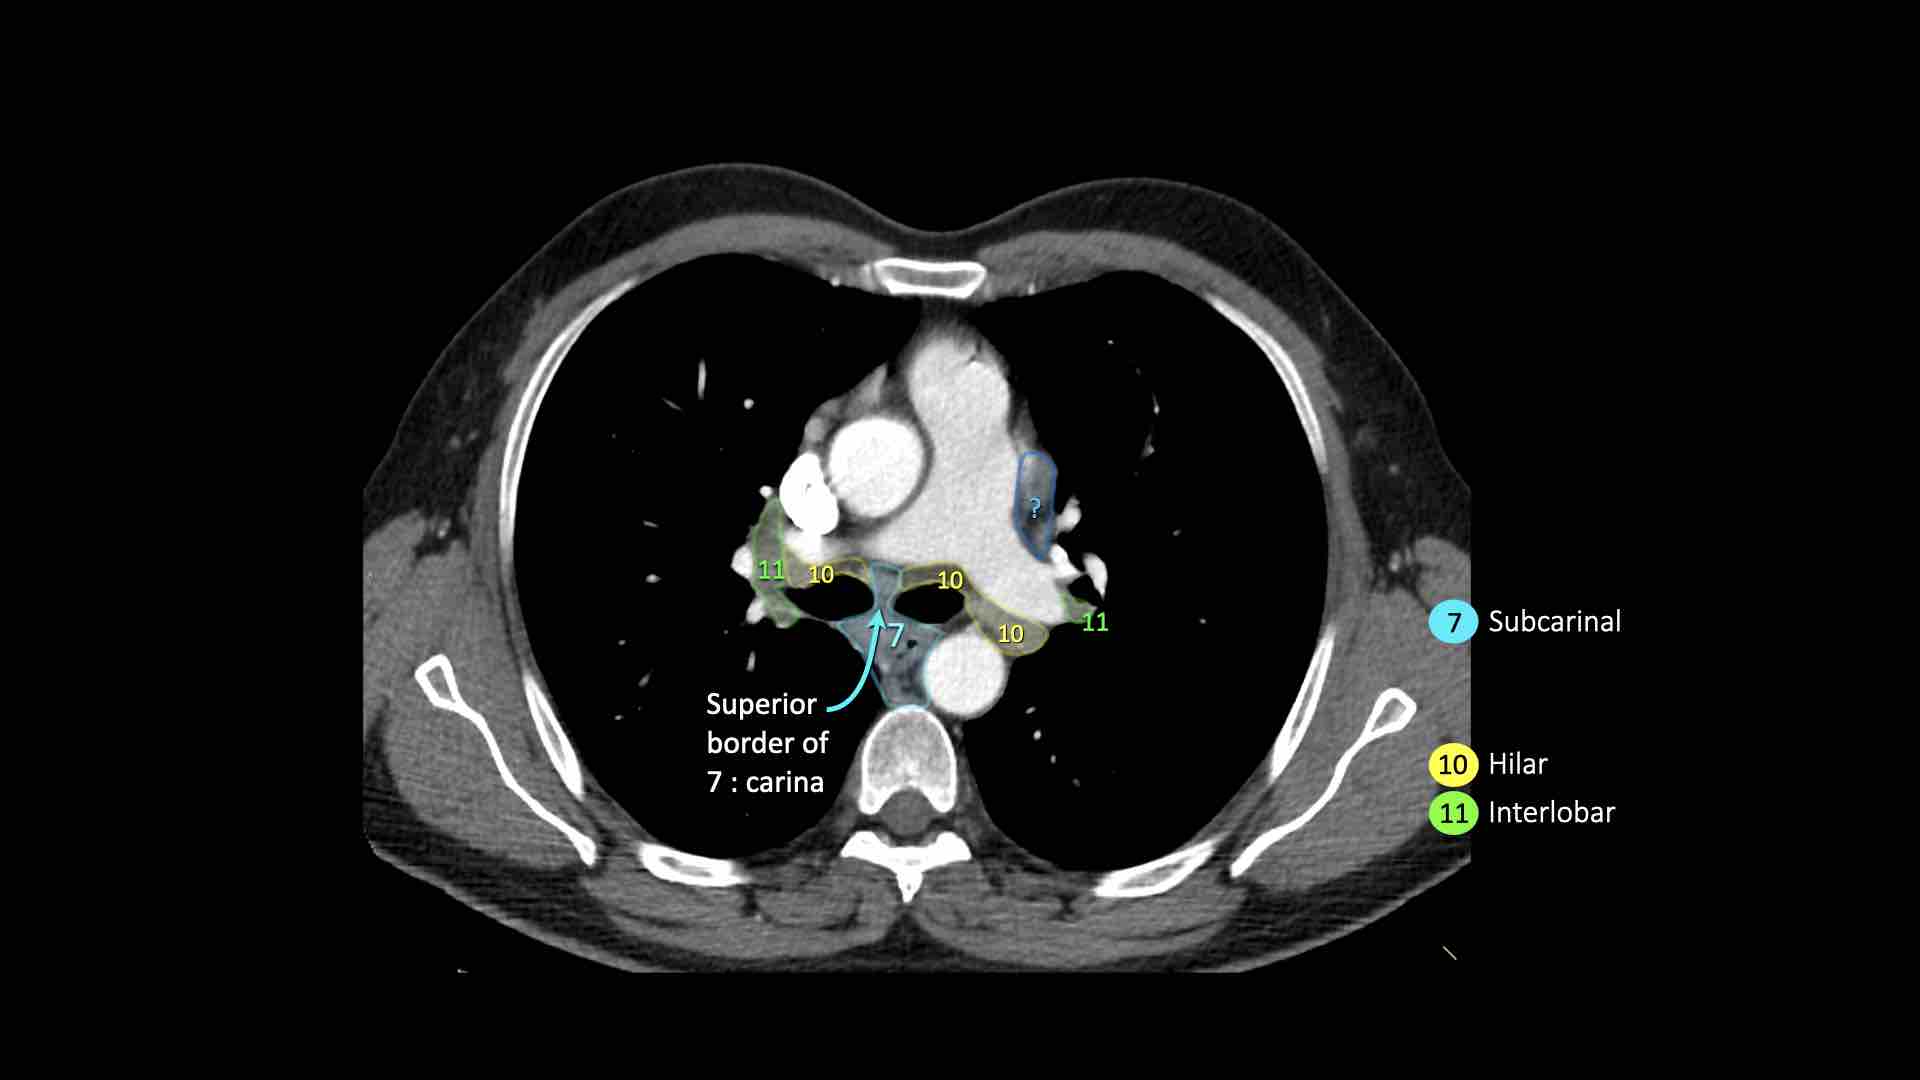

7.Dưới carina

7. Hạch dưới carina

Các hạch này nằm ở phía dưới carina khí quản, nhưng không liên quan đến phế quản thùy dưới hoặc các động mạch trong phổi.

Bên phải, chúng trải dài xuống đến bờ dưới phế quản trung gian.

Bên trái, chúng trải dài xuống đến bờ trên phế quản thùy dưới.

Bên trái là hạch dưới carina nhóm 7 nằm bên phải thực quản.

10. Hạch rốn phổi

Bao gồm các hạch tiếp giáp với phế quản gốc và các mạch máu rốn phổi.

Hạch rốn phổi là các hạch thùy gần, nằm ở phía xa so với nếp gấp màng phổi trung thất và các hạch kề phế quản trung gian bên phải.